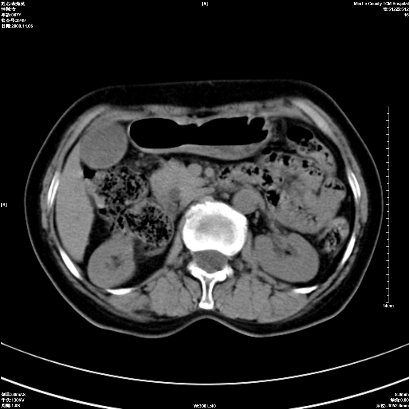

以下是引用卜一在2008-11-6 15:58:00的发言:[br]胰头略增大,胆总管扩张,末端渐行性狭窄。多考虑:胰头癌!建议增强!

以下是引用huangyinshan在2008-11-6 16:32:00的发言:[br]胰头略增大,胆总管扩张,末端渐行性狭窄。多考虑:胰头癌!建议增强!